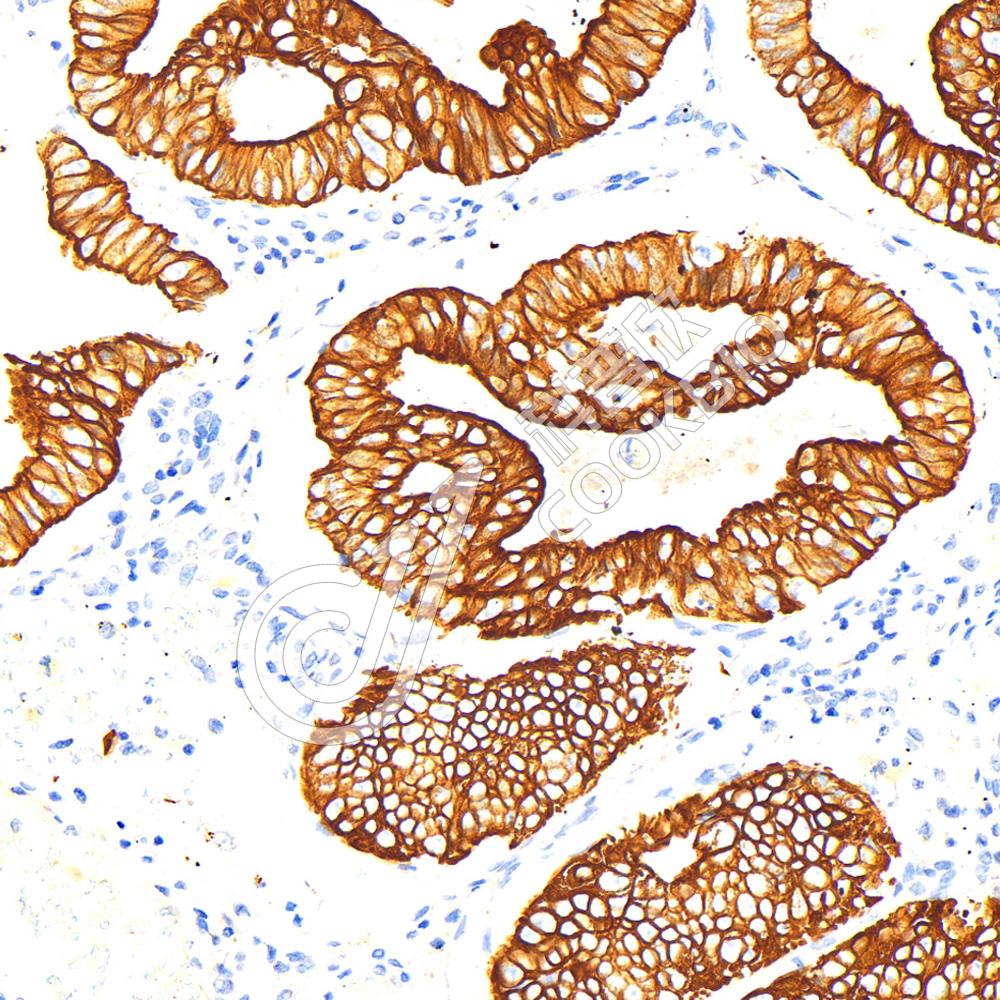

IHC检测Keratin 12/K12蛋白(货号 K1335460).

样品: 大鼠眼球, 4%多聚甲醛 (货号KSG1101) 固定12-24小时.

抗原修复: 柠檬酸抗原修复液(干粉, pH 6.0) (KSG1201), 98℃, 20分钟.

—抗: 1: 400稀释, 4℃ 孵育过夜.

二抗: S-vision免疫组化多聚二抗(山羊抗兔),即用型 (货号KB3906), 室温孵育20分钟.